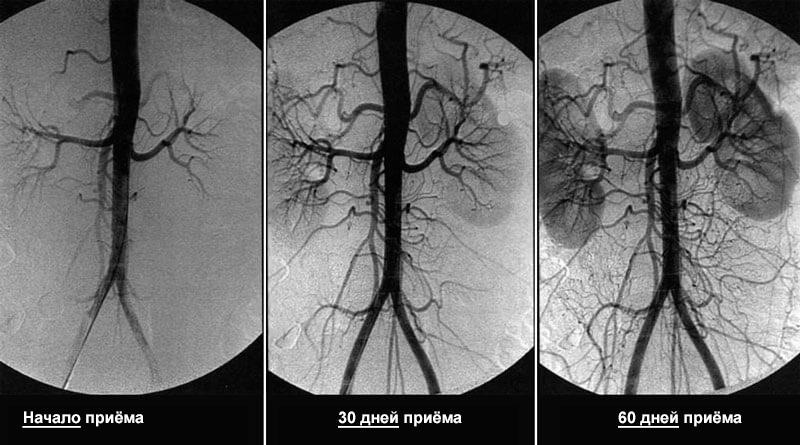

За 1,5 месяца приёма Кордис кровообращение восстанавливается на 99,71%

При этом кровообращение восстанавливается системно – во всех сосудах, артериях и капиллярах.

Растворяет атеросклеротические бляшки, кровяные тромбы и кальциевую известь. Увеличивает просвет сосудов до 99,71% от нормы и восстанавливает кровообращение.

– 1 раз в 5-7 лет, начиная с 40 лет для мужчин и с 45 лет для женщин. Длительность курса 1,5 месяца, при сильно выраженных симптомах нарушений кровообращения 2 месяца.